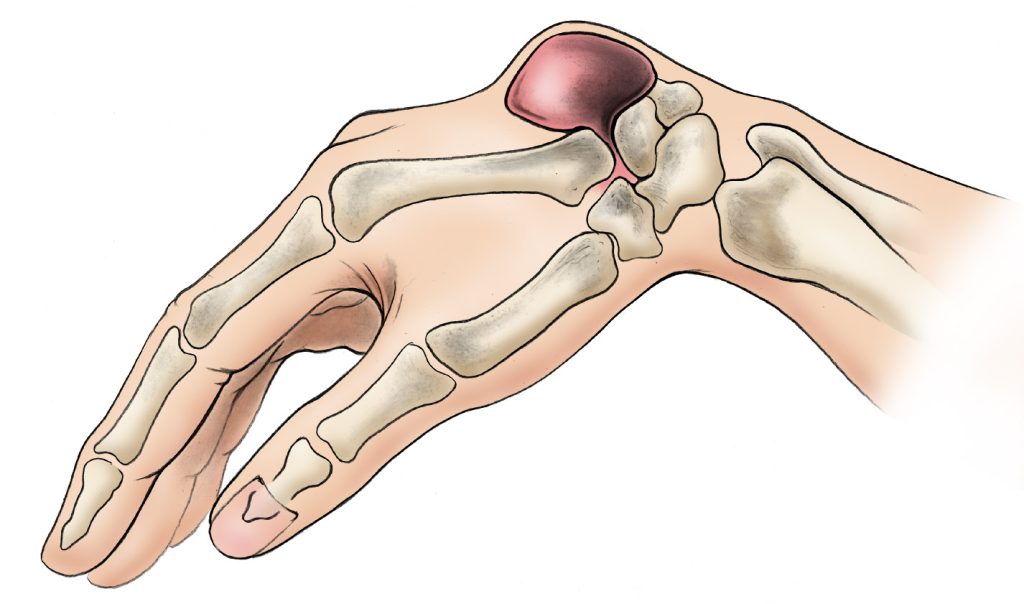

A ganglion cyst is a fluid-filled sac that forms when synovial fluid leaks from a joint or tendon sheath. These cysts vary in size and may grow larger with repetitive joint activity. Most ganglion cysts are round or oval and can range from pea-sized to larger, noticeable lumps.

- Visible lump or swelling near a joint or tendon